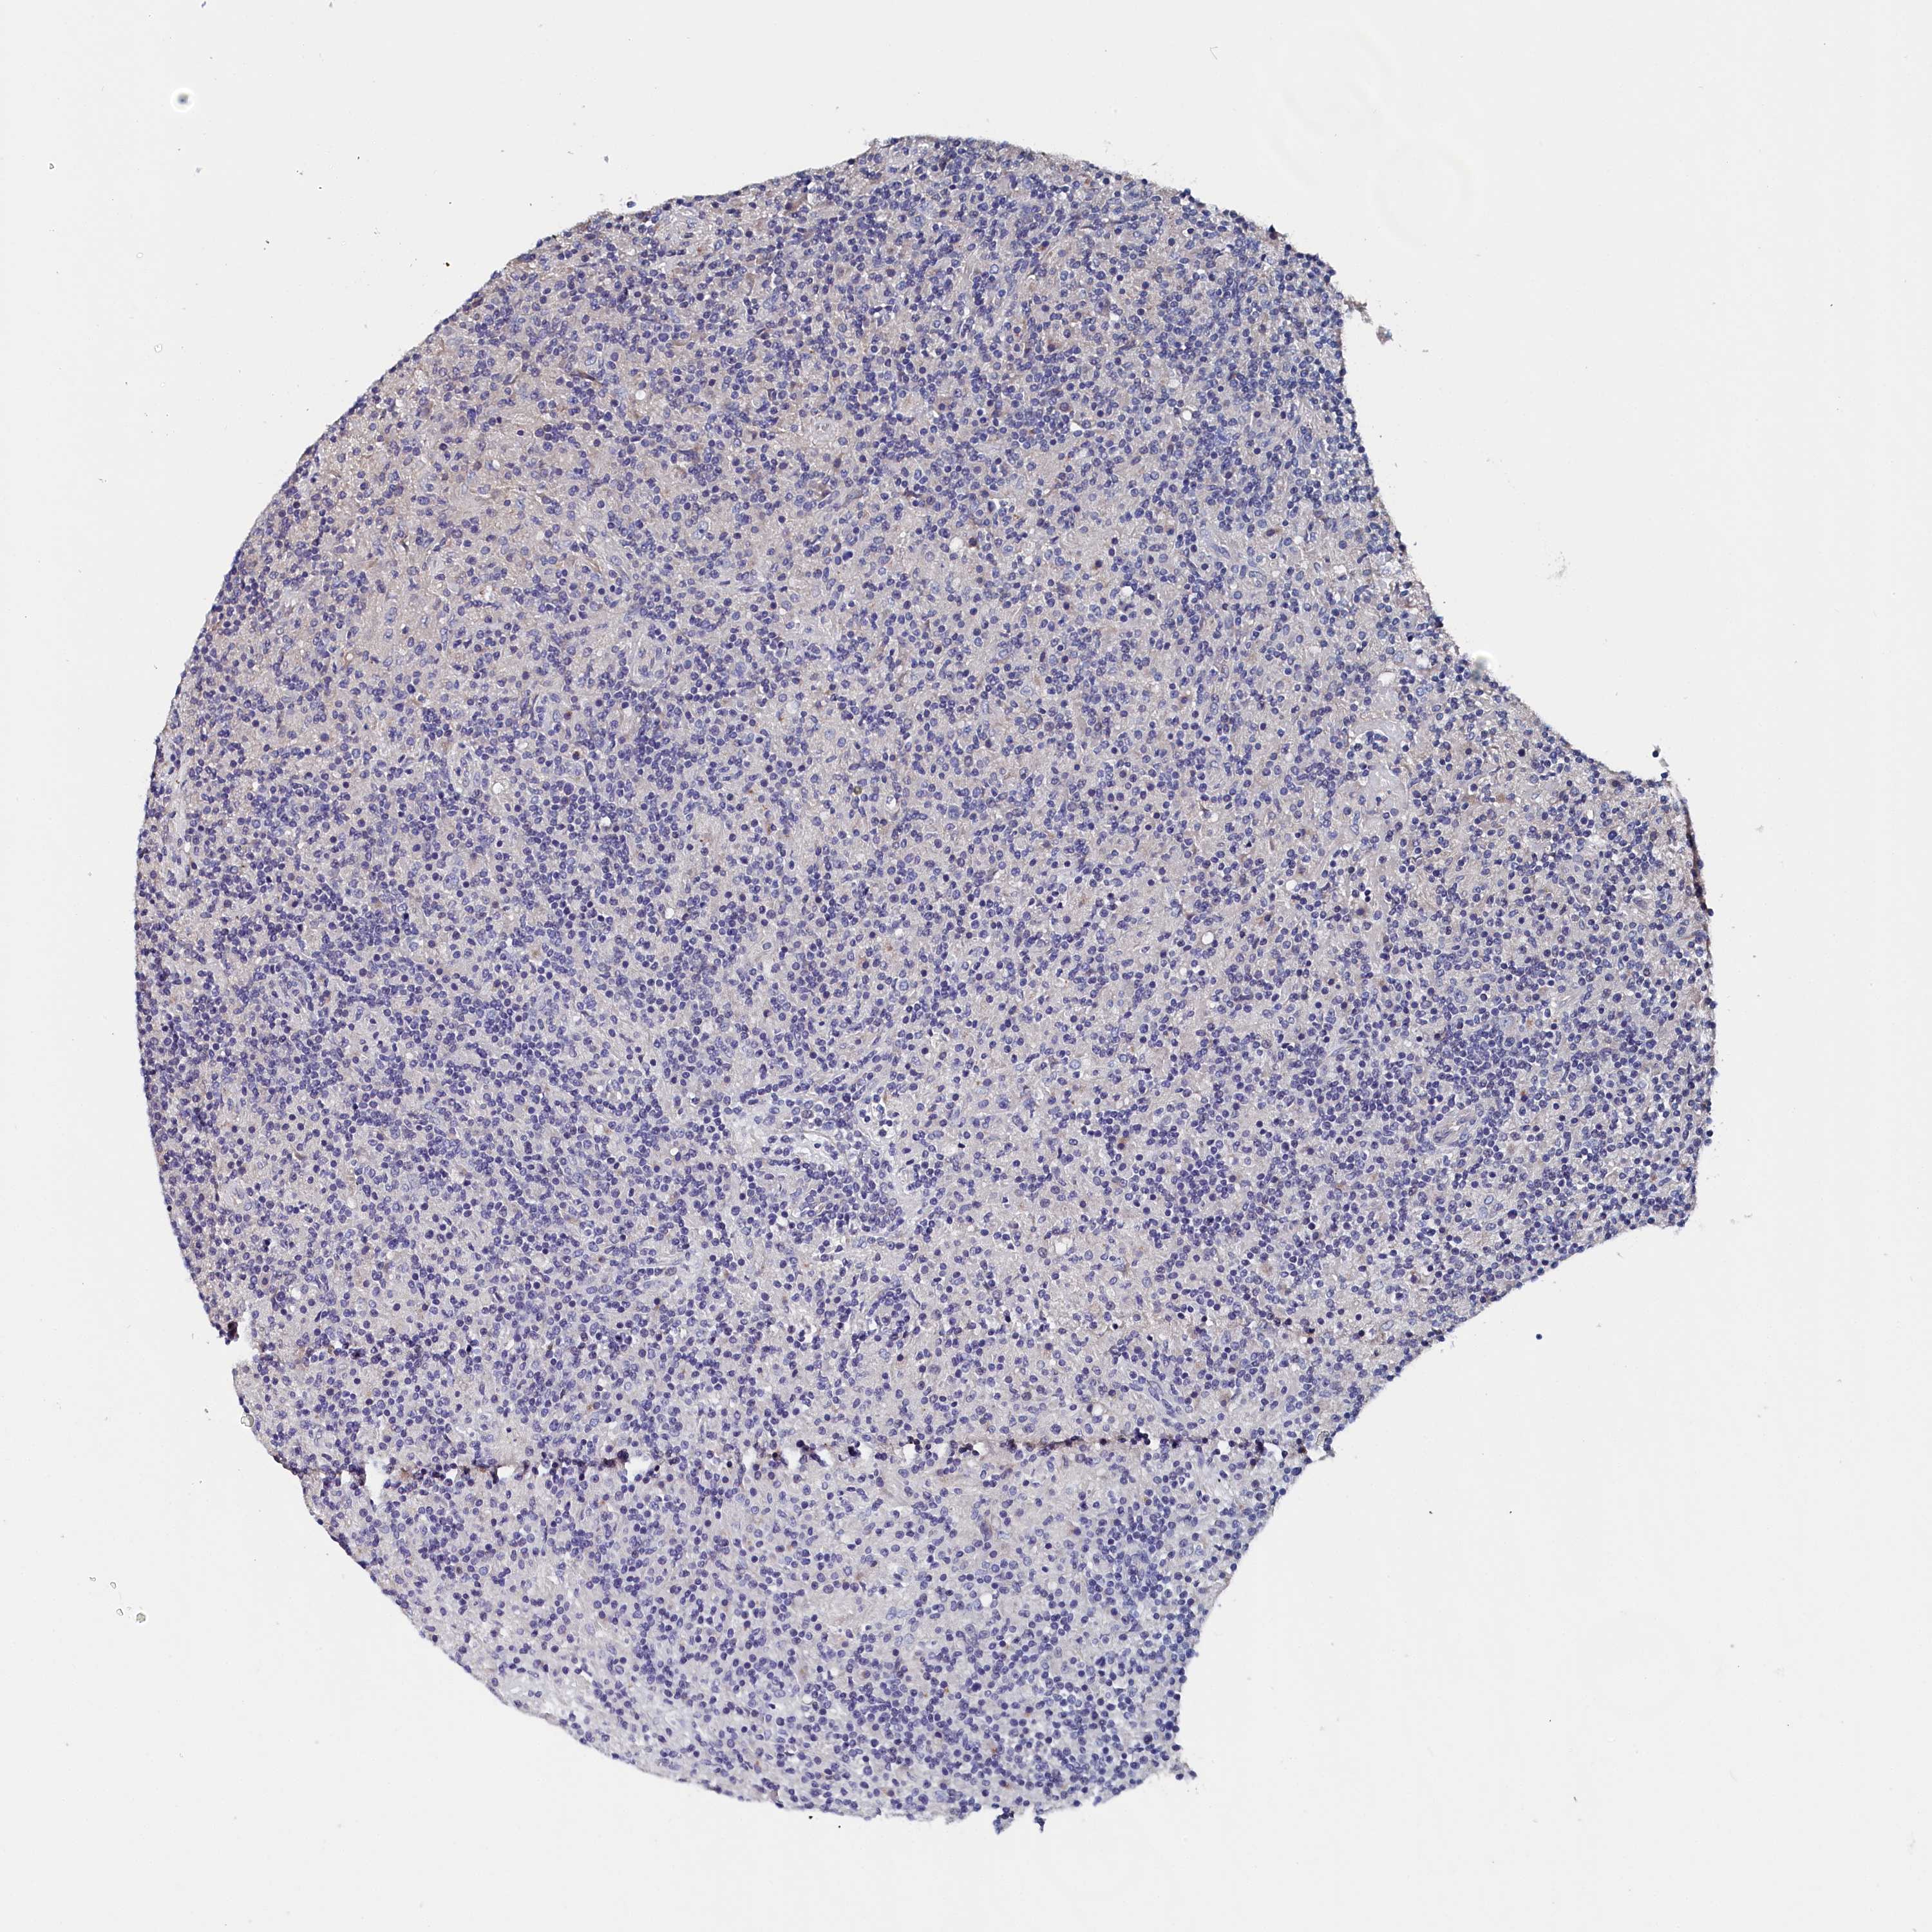

CANCER LYMPHOMA Show tissue menu

LYMPHOMA - Protein expressioni

A mouse-over function shows sample information and annotation data. Click on an image to view it in a full screen mode. Samples can be filtered based on level of antibody staining by selecting one or several of the following categories: high, medium, low and not detected. The assay and annotation is described here.

Each image is clickable and will lead to virtual microscopy that enables deeper exploration of all samples and also displays staining intensity scores, fraction scores and subcellular localization as well as patient and tissue information for each sample.

Antibody HPA038285

Antibody HPA058310

Hodgkin's disease, NOS

Malignant lymphoma, non-Hodgkin's type, High grade

Malignant lymphoma, non-Hodgkin's type, Low grade